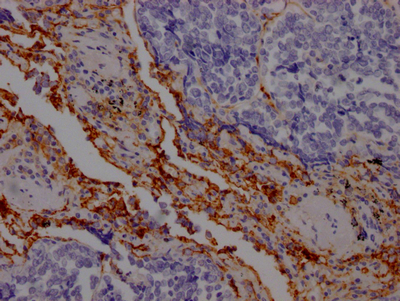

IHC image of CSB-RA162789A0HU diluted at 1:100 and staining in paraffin-embedded human lung cancer performed on a Leica BondTM system. After dewaxing and hydration, antigen retrieval was mediated by high pressure in a citrate buffer (pH 6.0). Section was blocked with 10% normal goat serum 30min at RT. Then primary antibody (1% BSA) was incubated at 4℃ overnight. The primary is detected by a Goat anti-rabbit IgG polymer labeled by HRP and visualized using 0.05% DAB.